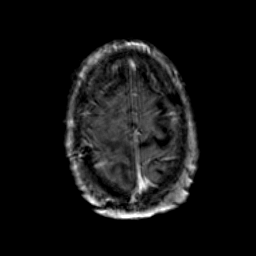

Glioma Overlay -- Slice #18

[Home][Help][Clinical] Slice 18